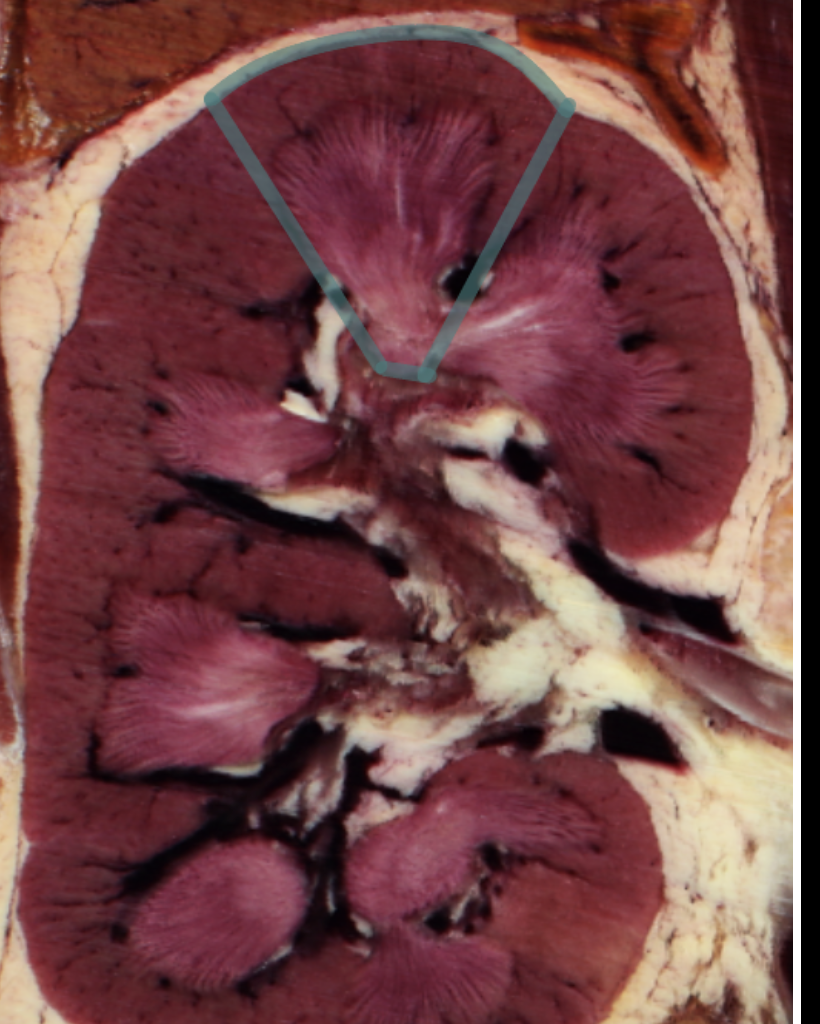

renal cortex

green

renal medulla

blue

renal columns

yellow

renal pyramids

purple

renal lobe

orange

renal papilla

minor calyx

teal

major calyces

renal pelvis

minor and major calyces